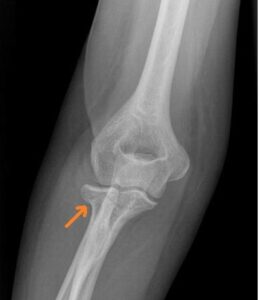

[toggle title=”Medial Epikondiler Kırıklar” state=”close”]

Çoğunlukla 10-14 yaş arası çocuklarda görülür.

Yaralanma direkt travma sonucu olabileceği gibi fleksör kas grubunun oluşturduğu avülsiyon sonucu ya da dirsek çıkığına sekonder de olabilir.

Medial epikondil kırıklarının yarısına yakınında eşlik eden dirsek çıkığı da görülür. Bu hastalarda dirsek redükte edildiğinde medial epikondil kırığı da redükte olur.

Kırık parçanın eklem içinde kalması nedeniyle redüksiyon yapılamayan durumlarda ya da kırığa eşlik eden ulnar sinir yaralanması varlığında cerrahi tedavi gerekir.